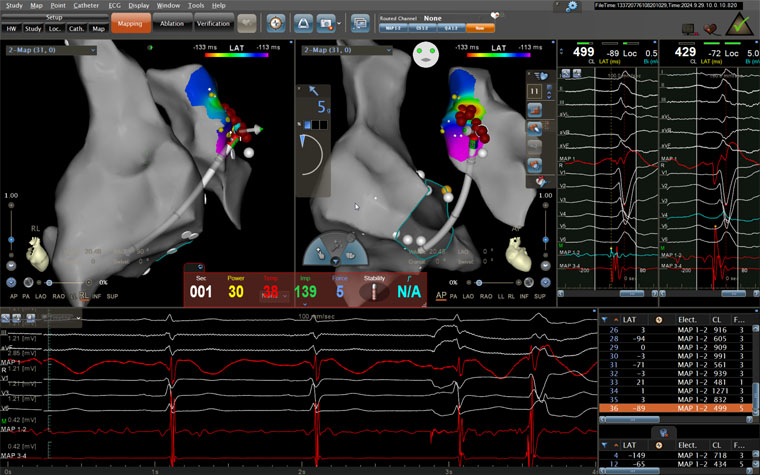

术中患者射频消融情况

手术当日,医护人员连接多导电生理仪和CARTO三维标测系统,对病人进行术前消毒,局麻后穿刺股静脉,操作ST消融导管至右房,建立右心三维解剖。术中,姚铁柱副主任操作ST消融导管经三尖瓣进入右室流出道,于右室流出道后游离壁标测到最早激动靶点,诱发室早形态与原体表心电图室早形态相同,给予放电消融,患者室早消失;继续行冠脉造影术,导管造影结果显示,前降支中段可见约50%局限性狭窄。术毕,患者安返病房,心电图示为“窦律规整”;继续给予心电监测,患者无室早出现,心慌、气短症状消失。根据冠状动脉造影结果对其调节药物治疗,患者胸痛、背痛症状得到缓解。术后仅不到两日,患者便顺利出院。